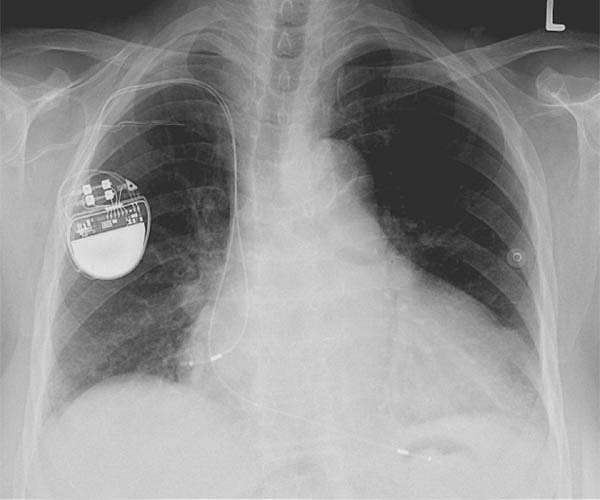

The new material could be used to develop devices that convert blood pressure into a power source for pacemakers.

The material's potential biomedical applications include internal biosensors and self-powering biotechnologies, such as devices that convert blood pressure into a power source for pacemakers.